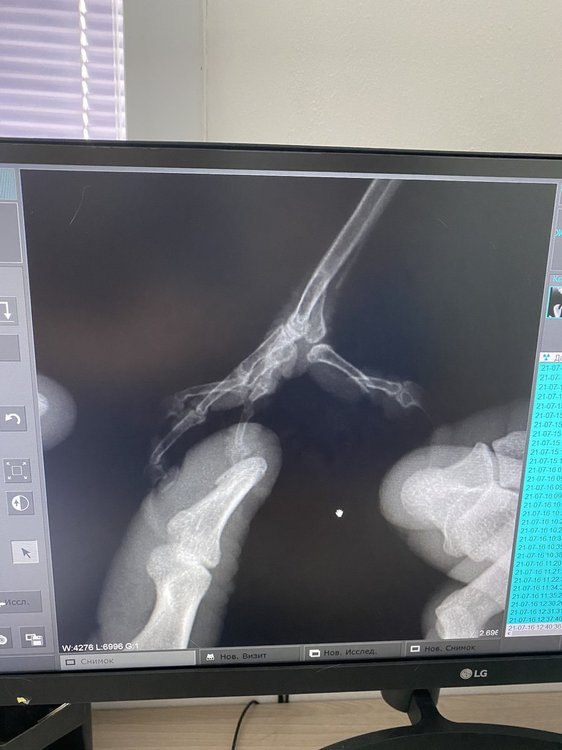

@OFA здравствуйте! У нас новая проблема с воронёнком. Он сломал задний пальчик (залетел на сложённую бельевую сушилку, палец застрял между  креплениями, повезло что были дома и вовремя обнаружили его, так как не мог сам освободиться).

Только что пришли с приема от врача, я думала что ему наложат шину. Врач сказал, что это ни к чему и что все должно зарасти само (но палец у нас свёрнут вбок, я боюсь как бы он не сросся неправильно). Кое как нам сделали рентген, фотографии прикрепляю (попросила ещё их сделать рентген туловища для интереса, но качество оставляет желать лучшего). Также прикрепляю фотографии назначений.